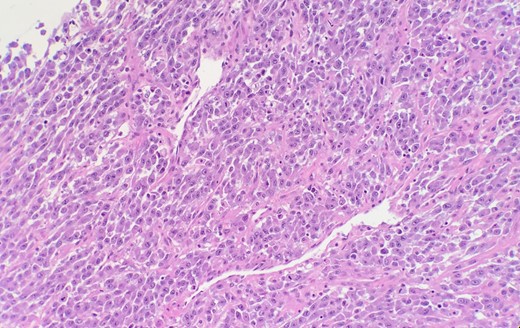

The histopathology of the bladder revealed stage IIIA (T3b) invasive and poorly differentiated urothelial cell carcinoma (Fig. 1) with areas of mullerian and squamous cell carcinoma features (Fig. 2). Histology also showed areas of necrosis and acute inflammatory changes.

Microscopic examination reveals high grade urothelial carcinoma.